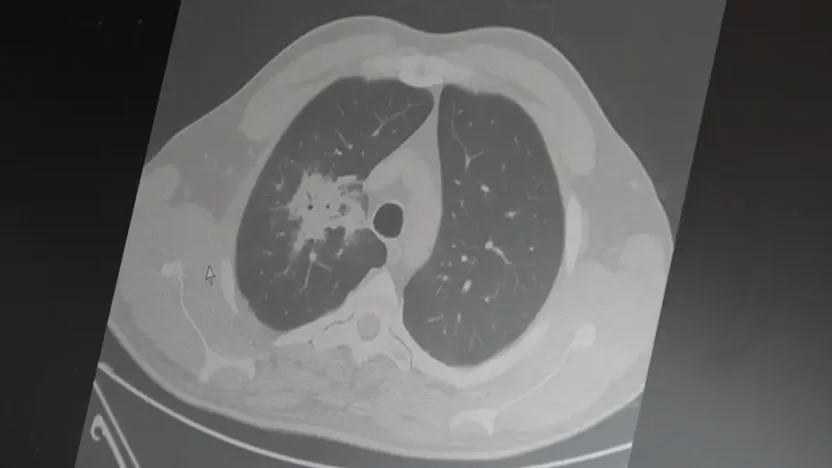

Prof. Dr. Şevket Özkaya, elektronik sigaralarla ilgili beklenen ’20 – 30 yıllık kullanım’ süresinin dolduğunu, 100’den fazla çalışmanın analiz edildiğini ve net olarak kanser riskini artırdığını söyledi.